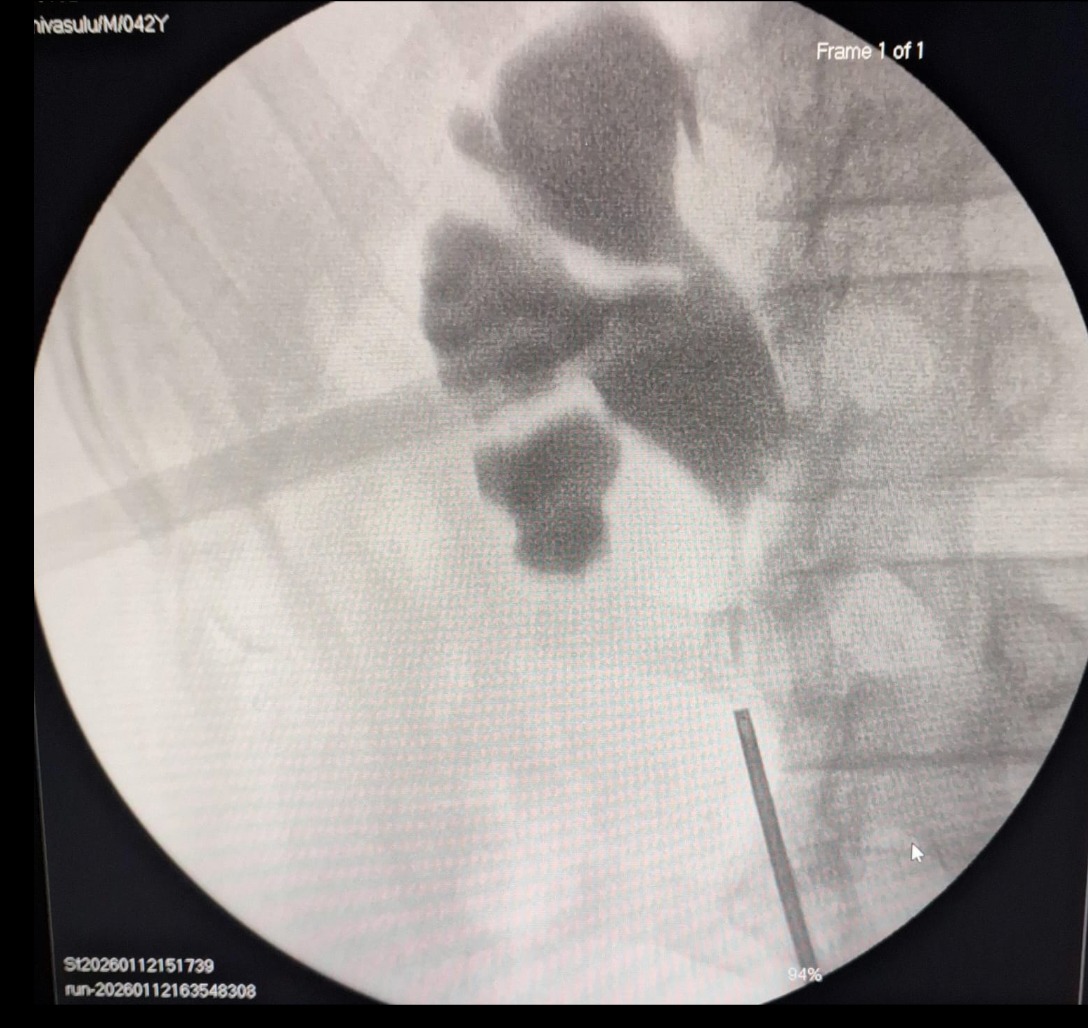

🔹 PCNL